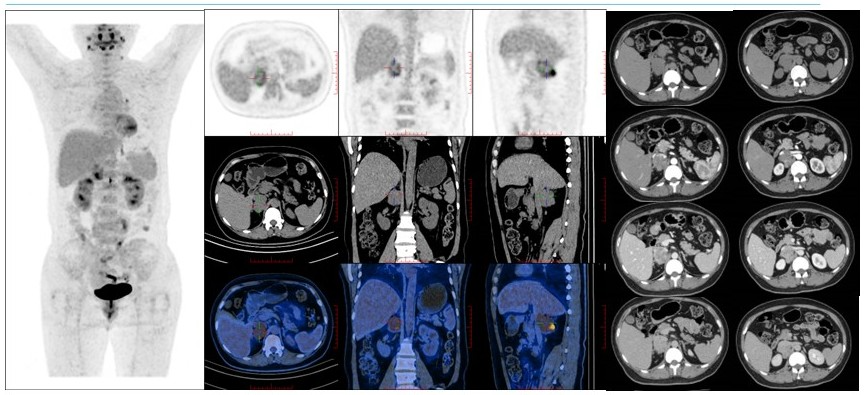

病例(11为一中年女性,体检发现右肾上腺肿物就诊;增强CT检查示右侧肾上腺区肿块,增强扫描呈明显不均匀强化伴多发小血管累及下腔静脉并突入腔内18F-FDG PET/CT示肿物代谢不均匀增高;肾上腺肿物)切除病理为平滑肌肉瘤

病例(12为一老年男性,体检发现左肾上腺肿物就诊,入院后监测血压轻度升高实验室检查示皮质醇水平轻度升高;增强CT检查示左侧腹膜后占位呈轻度强化,占位周围见片状低密度灶,MRIT1WIT2WIDWI高低混杂信号,周围见片状T1WI低信号、T2WI高信号灶;18F-FDG PET/CT示肿物代谢明显增高;(左肾上腺肿物)切除病理为神经纤维瘤。

病例(13为一中年女性,间断心悸检查发现左肾上腺结节就诊,既往乳腺癌保乳术后;外院儿茶酚胺及其代谢产物检测提示多项指标升高,我院复查较前下降增强CT检查示左侧肾上腺三枚软组织密度结节伴中等强化;18F-FDG PET/CT68Ga-奥曲肽显像示三枚结节呈SSTR明显高表达、代谢无或轻度增高;(左肾上腺肿物)切除病理为节细胞神经瘤

病例(14为一老年女性,体检发现左肾上腺肿物就诊增强CT检查示左侧肾上腺区不规则团片状软组织密度灶,增强扫描呈轻度强化,MRIT1WI低信号、压脂T2WI稍高信号、DWI高信号;18F-FDG PET/CT示肿物代谢轻度不均匀增高;(左肾上腺肿物)切除病理为结外边缘区淋巴瘤

病例(15为一中年男性,高血压病史,检查发现双侧肾上腺肿物;实验室检查示肾素、血管紧张素、醛固酮水平不同程度升高,卡托普利试验阴性,血皮质醇水平8am略升高,尿游离皮质醇明显升高;增强CT见双侧肾上腺分叶状肿块伴明显不均匀强化;18F-FDG PET/CT示双肾上腺占位代谢异常增高,99mTc-曲肽及131I-MIBG显像均为阳性;(双肾上腺肿物)切除病理均为嗜铬细胞瘤。